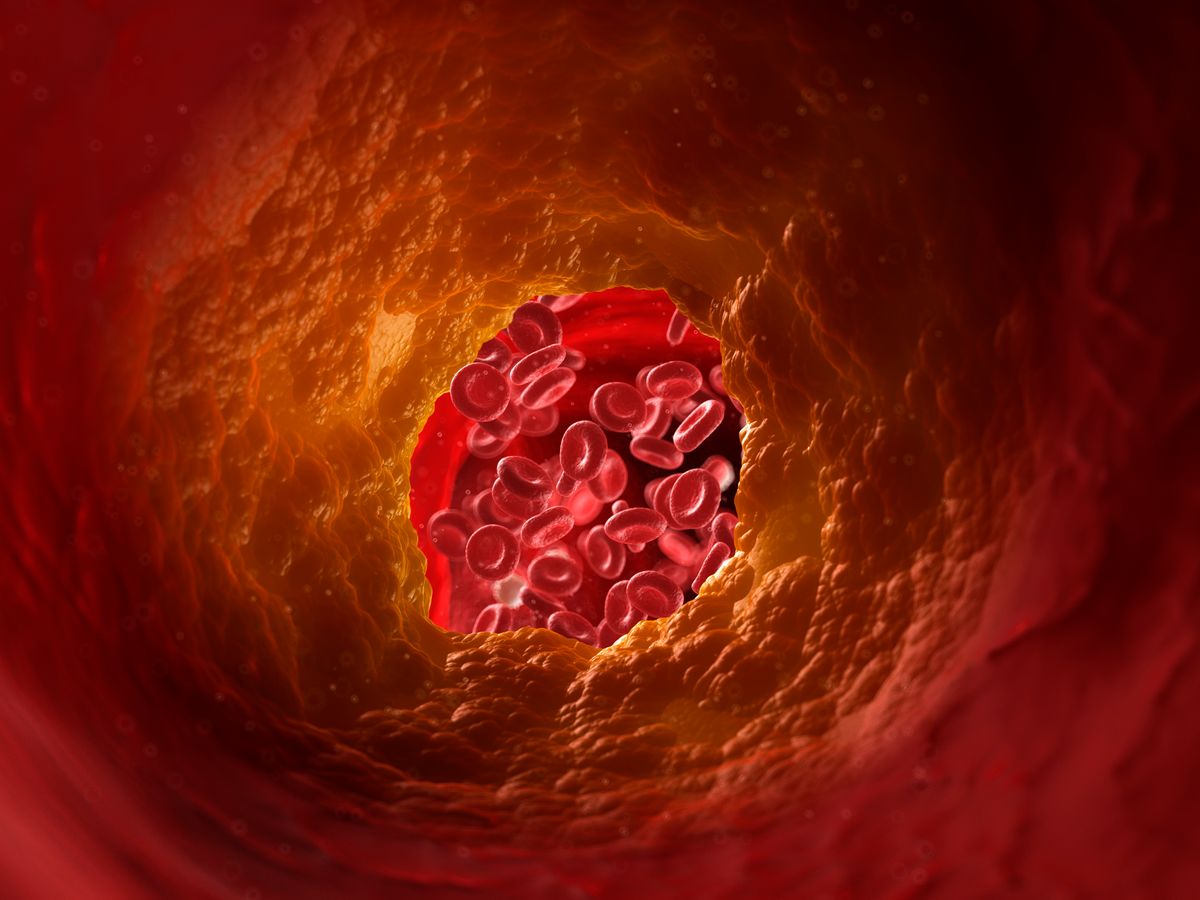

Having high cholesterol means you have too much of a fatty substance known as cholesterol in your blood. Over time, this can cause the arteries to harden and narrow, making it more difficult for blood to pass through.

This is a major risk factor for medical emergencies such as heart attacks and strokes. While many people with high cholesterol will be prescribed medication to help, it is also possible to improve your levels through changing your diet.

Having high cholesterol can cause your arteries to narrow and harden(Image: Getty)